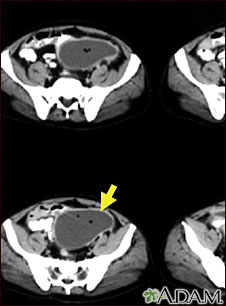

TC de la pelvis que muestra una gran masa dentro del abdomen.